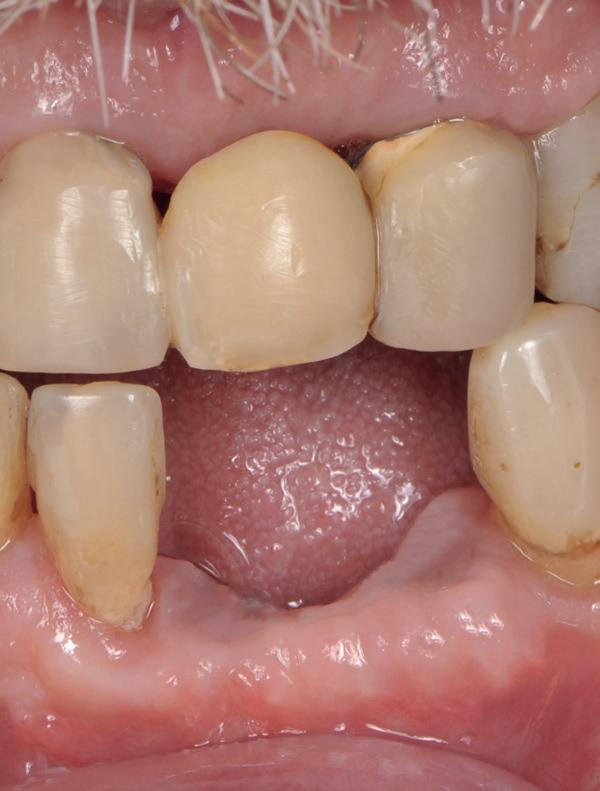

Casus

De patiënt, een 70-jarige man, had in het verleden tandheelkundige zorg ontvangen die zich kenmerkte door een ad hoc benadering. Er was geen sprake van een overkoepelend behandelplan of lange termijnvisie. De patiënt had naar eigen zeggen jarenlang niets

1. Studiofoto intake

aan zijn gebit gedaan behalve pappen en nathouden. Tandheelkundige zorg werd enkel verleend wanneer er zich een probleem voordeed (afbeelding 1, 3, 5).

Een 47-jarige collega presenteert zich in onze verwijspraktijk voor endodontie. Hij heeft enige tijd geleden zijn kroon op de 11 laten vervangen (afbeelding 1). Omdat er geen klinische en röntgenologische aanwijzingen waren voor een periapicale laesie of een insufficiënte wortelkanaalbehandeling van de 11, werd besloten de endo, die dateerde van meer dan 30 jaar geleden, niet te reviseren (afbeelding 2). Tijdens een routinematige gebitsreiniging constateert zijn mondhygiënist een pocket van 7 mm aan de mesiopalatinale zijde van 11 (afbeelding 3). De nieuwe kroon wordt tijdelijk gecementeerd, en omdat

1: Klinische foto van bovenfront